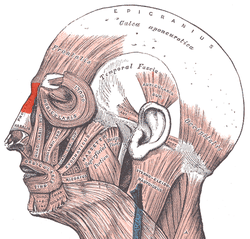

Muscles of the head, face, and neck. (Procerus visible at upper left, at top of nose.) | |

The procerus is a small pyramidal slip of muscle deep to the superior orbital nerve, artery and vein. Procerus is Latin, meaning tall or extended.

The procerus arises by tendinous fibers from the fascia covering the lower part of the nasal bone and upper part of the lateral nasal cartilage.

It is inserted into the skin over the lower part of the forehead between the two eyebrows on either side of the midline, its fibers merging with those of the frontalis.[1]